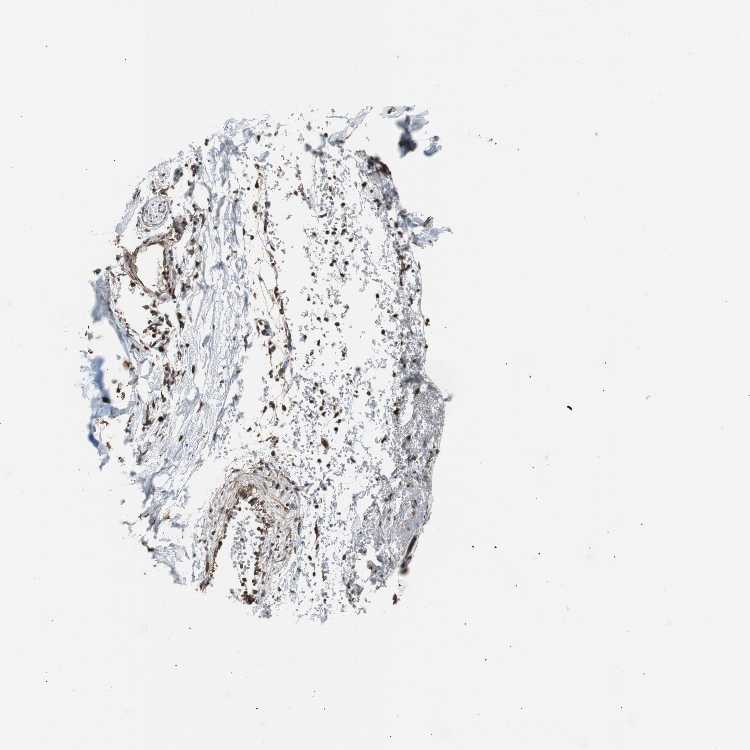

ADIPOSE TISSUE - Antibody stainingi

Antibody staining in the annotated cell types in the current human tissue is reported as not detected, low, medium, or high, based on conventional immunohistochemistry profiling in selected tissues. This score is based on the combination of the staining intensity and fraction of stained cells.

Each image is clickable and will lead to virtual microscopy that enables deeper exploration of all samples and also displays staining intensity scores, fraction scores and subcellular localization as well as patient and tissue information for each sample.

Antibody HPA006018

Adipocytes Low